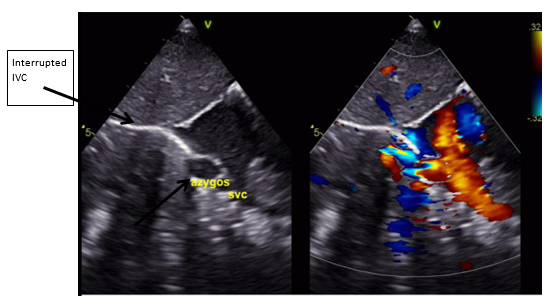

Postnatal ECHO revealed an Interrupted IVC (Figure 1) with venous return via the azygos vein (Figure 2 & Figure 3), draining into the superior vena cava (SVC), hepatic veins draining directly into the right atrium (RA), SVC draining into the RA and a small patent foramen ovale (PFO) with left-to-right shunting with normal cardiac anatomy with no abnormalities of the valves, aortic arch, outflow tracts, and no outflow tract obstruction.

The infant was reviewed in the Pediatric Cardiology clinic subsequently and was asymptomatic from a cardiac standpoint. Repeat ECHO showed good biventricular systolic function, intact interatrial and interventricular septae, and absent IVC at the liver level (Interrupted IVC). Hepatic veins drained directly into the Right atrium (RA), while the azygos vein compensated with normal flow into the SVC. The pulmonary veins, numbering four, drained into the left atrium, and a single right-sided SVC drained into the RA. The aortic arch was unobstructed, and the pulmonary arteries were confluent and appropriately sized.